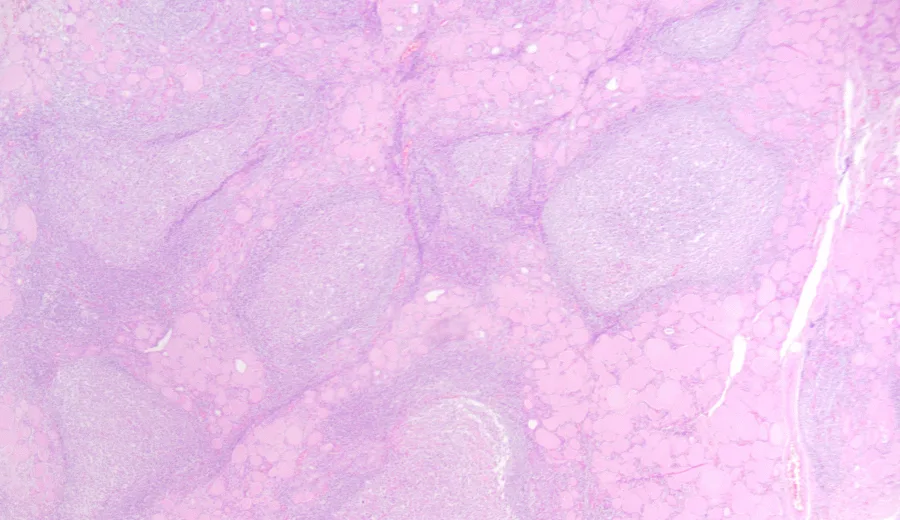

Fine Needle Aspiration Cytology (FNAC)

- Cytology will show significant lymphocytic and plasma cell infiltration with destruction of thyroid follicles. There will be presence of fibrotic tissue, Askanazy (Hurthle) cells – oxyphilic epithelial cells with granular cytoplasm.

- Histopathological variants of Hashimoto thyroiditis have been described, including:

- Atrophic and fibrotic variants

- Riedel thyroiditis

- Immunoglobulin G4 (IgG4)-related thyroiditis